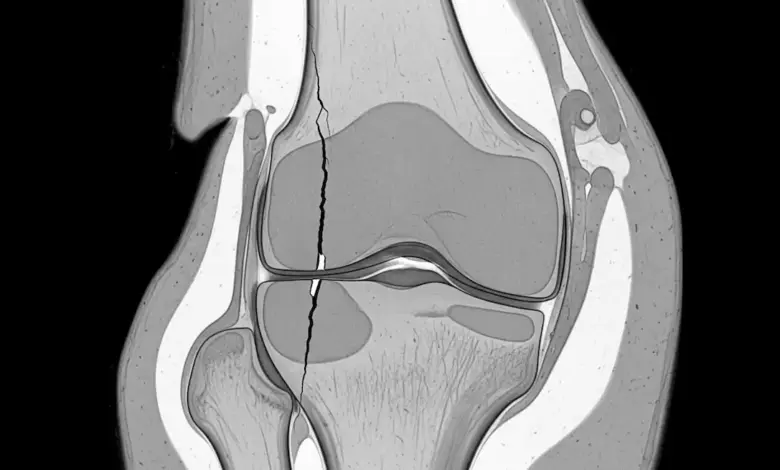

A fissura condral profunda na faceta medial da patela é um achado que exige atenção clínica, sobretudo quando o paciente apresenta dor anterior no joelho, limitação para agachar, desconforto ao subir escadas e sensação de atrito durante o movimento.

Na prática, esse tipo de lesão indica comprometimento importante da cartilagem articular em uma área que participa diretamente do deslizamento da patela sobre o fêmur.

Quando o laudo aponta fissura profunda, existe uma quebra dessa superfície, com maior exposição ao impacto mecânico e pior distribuição de carga dentro da articulação.

A ressonância magnética é o exame que melhor mostra a profundidade da lesão condral, sua localização e possíveis alterações associadas.

Ela ajuda a entender se existe comprometimento mais focal, desgaste mais amplo ou envolvimento de outras estruturas do joelho.